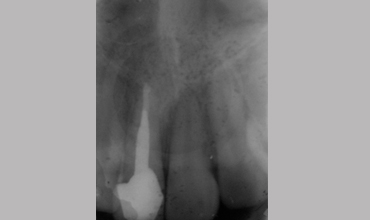

Management Of Fractured Tooth With Cast Post & Core